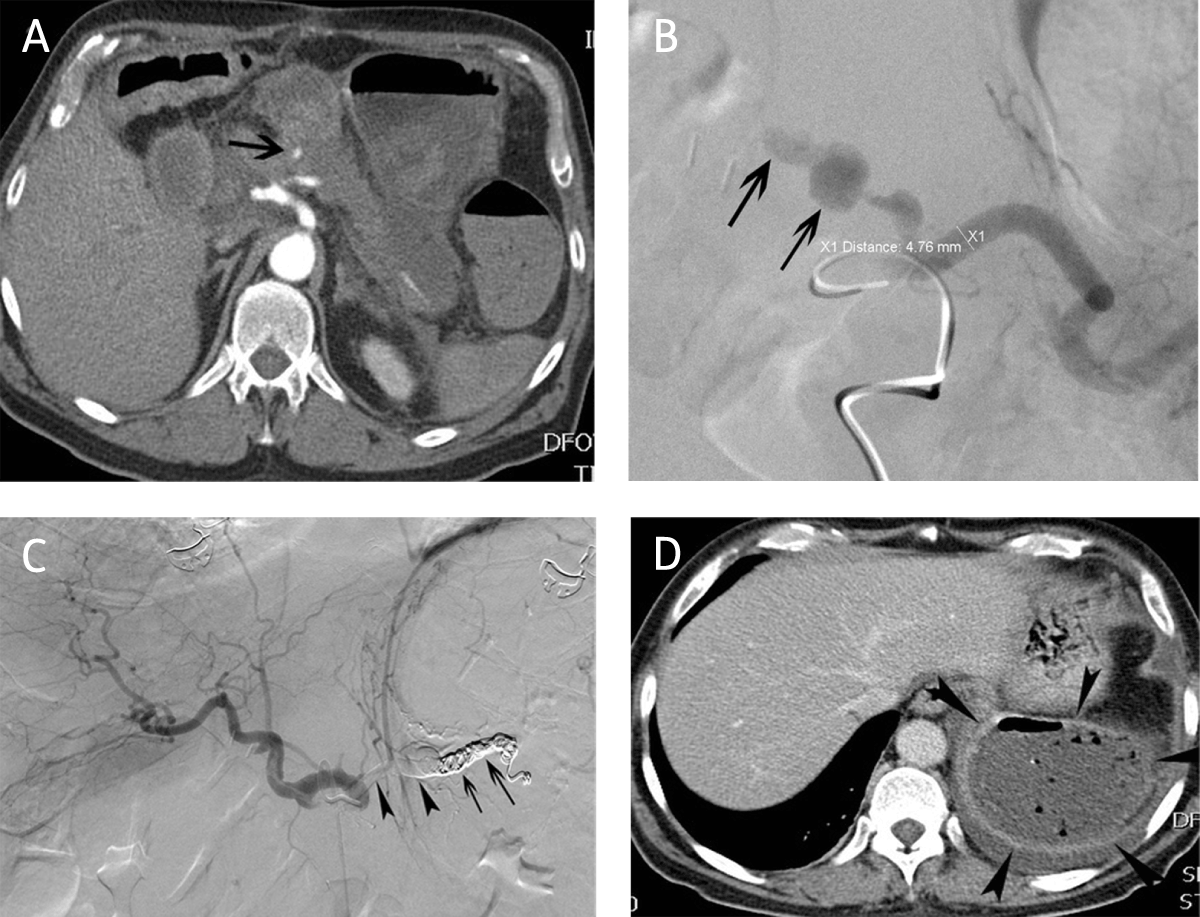

Figure 3

Main splenic artery embolization for postoperative hemorrhage. (A) CT-angiography in a 64-year-old man 19 days after pancreatico-duodenectomy revealed contrast extravasation (arrow) in the proximal part of the main splenic artery. (B) Corresponding selective splenic arteriography confirmed the contrast extravasation and a pseudoaneurysm (arrows). (C) Embolization of the hemorrhage was performed with a combination of coils (arrows) and glue (arrowheads). (D) CT eight days after embolization revealed multiple air bubbles in a completely necrotic splenic tissue compatible with abscess.